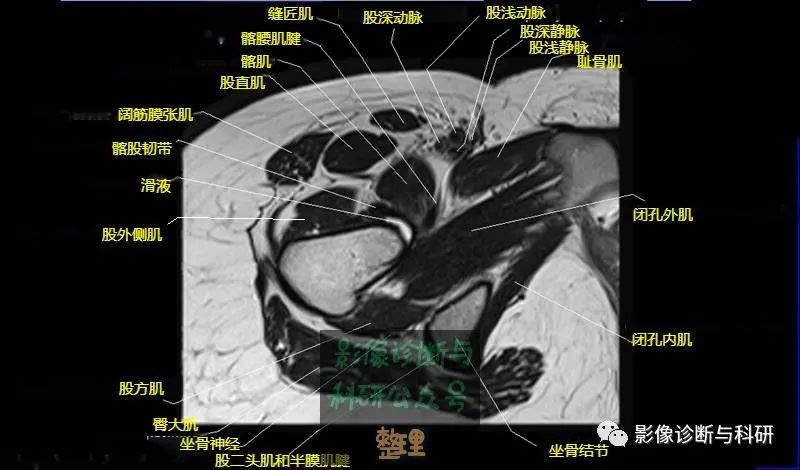

髋关节MR轴位详细标注